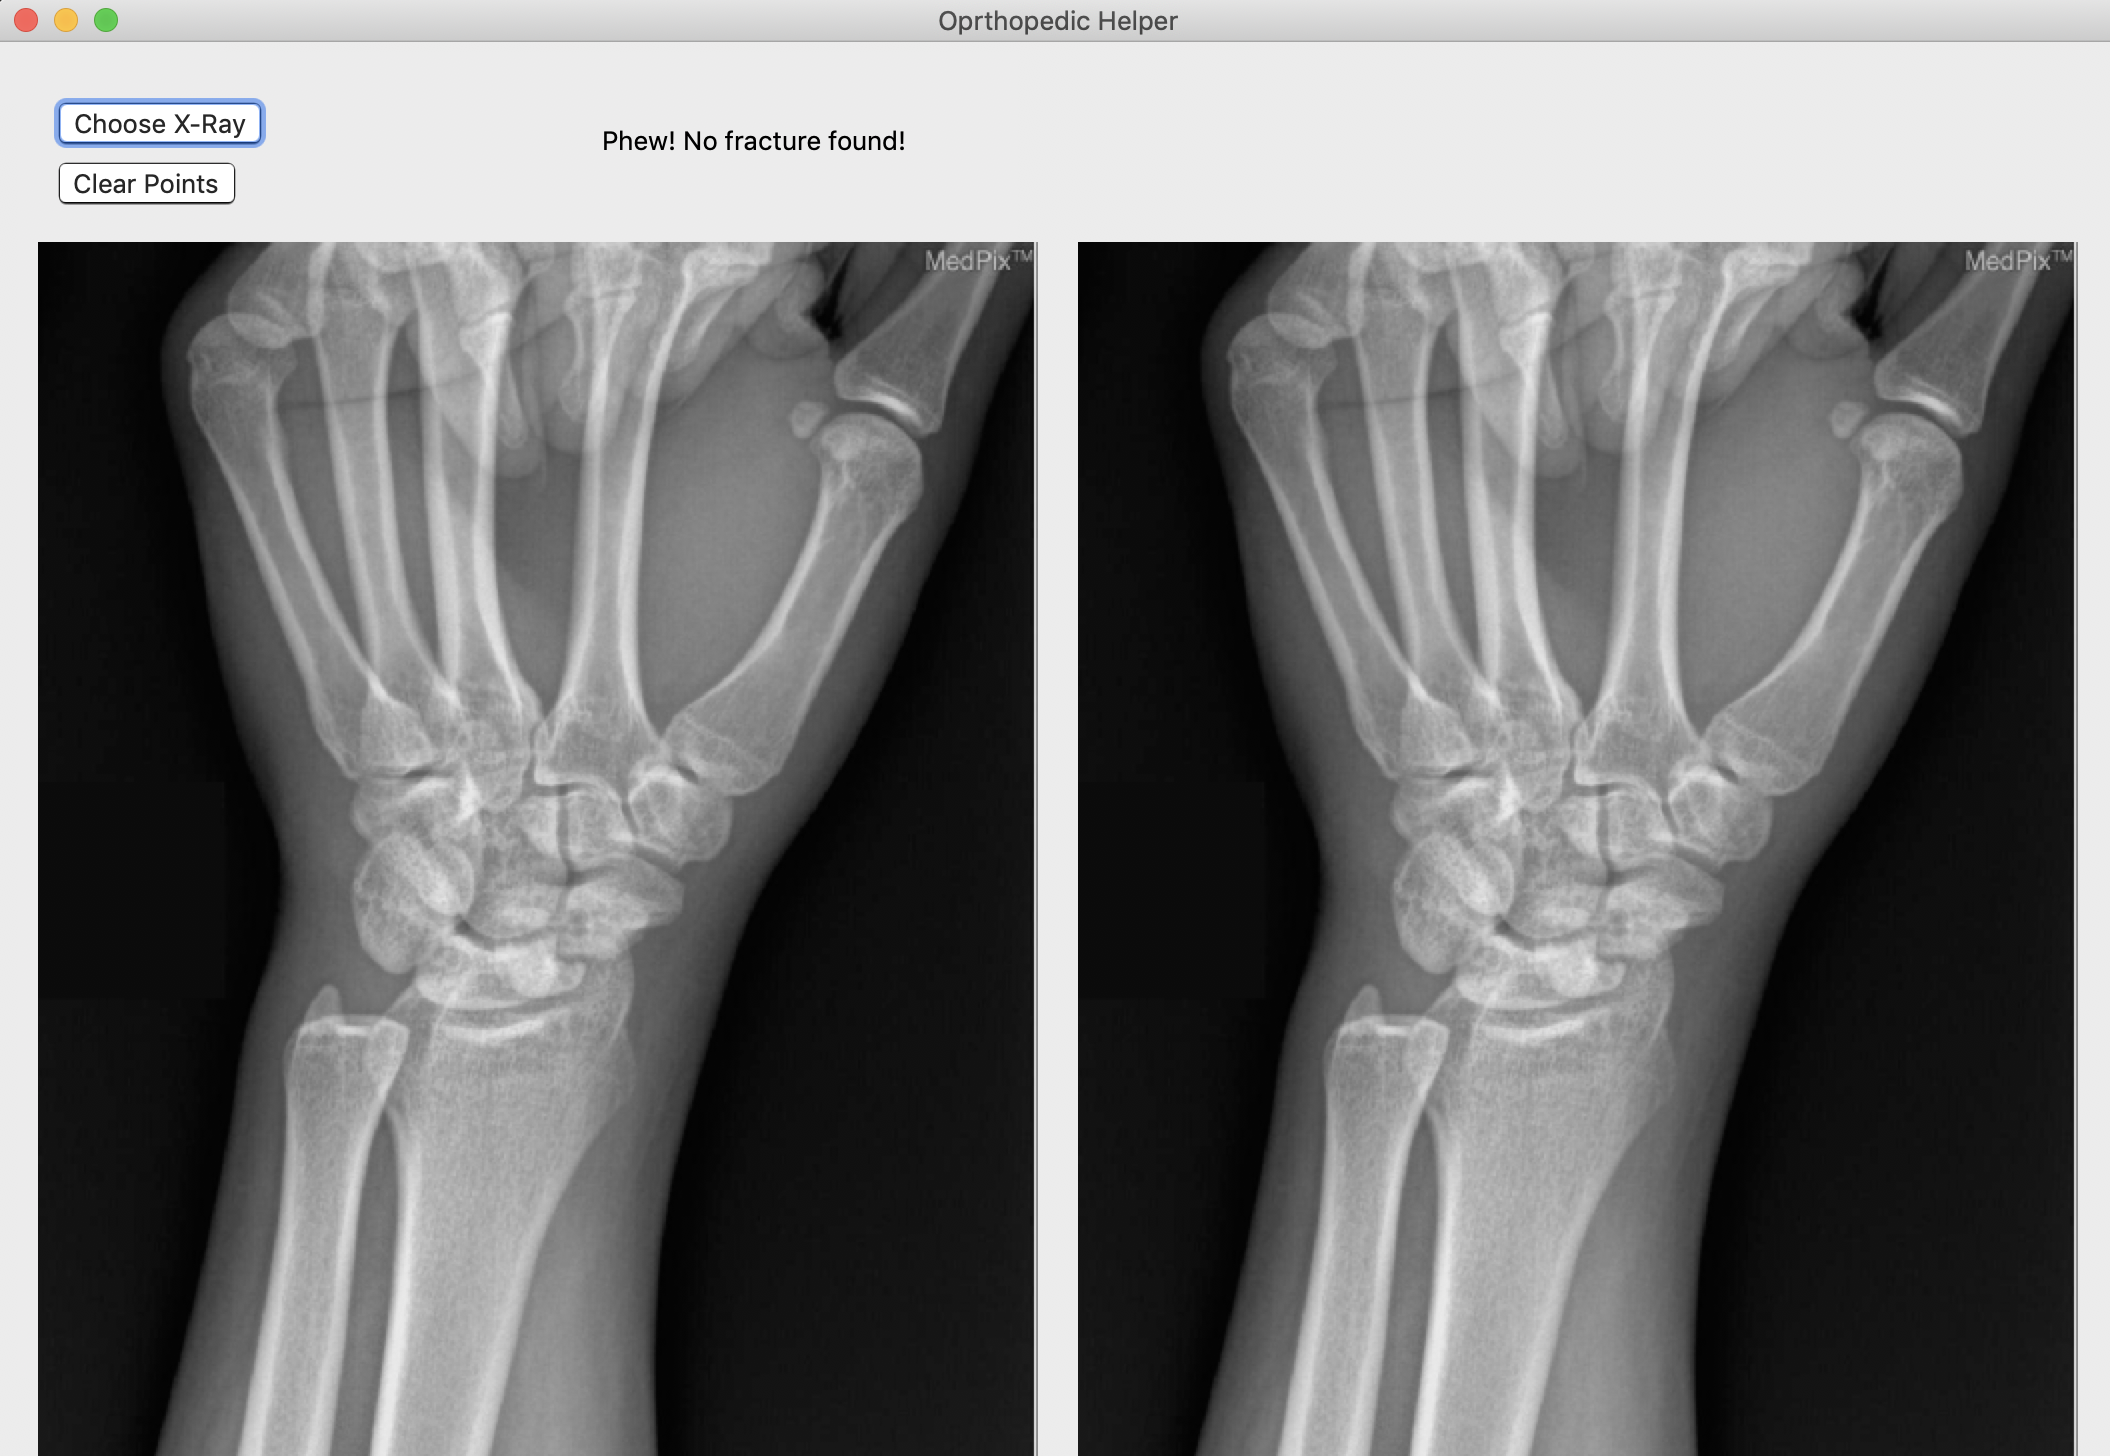

Broke Detector is a simple tool to help analyze the site of wrist injury. It helps doctors decide a) whether the bones are broken or not (which is admittedly very simple for humans, but not for computers) and b) provides tools such as a protractor to provide an objective measurement of how misaligned bones are. Broke Detector aims not to replace the orthopedist, but to aid them.

The actual detection algorithm is the guts of this project (no machine learning involved). The process is as follows: Thresholding: Reasons for this will be listed in the next section, we did this using color histograms to determine the percentile of certain pixel values. Edge detection: We used a simple Söbel kernel (however, not the default opencv one) to handle edge detection, as it was simple to detect only horizontal edges. Hough transform: This is the guts of the algorithm, which decides where horizontal lines are in the X-Ray. It sounds dumb, but choosing the lowest isolated horizontal line almost always results in finding the break in the bone. Flask: We developed a locally hosted web application which supports uploading from the computer. The HTML formatted site displays the results of the Python calculations.

It works! Surprisingly. Certainly, I didn't expect to have this kind of success with a non-ML solution.